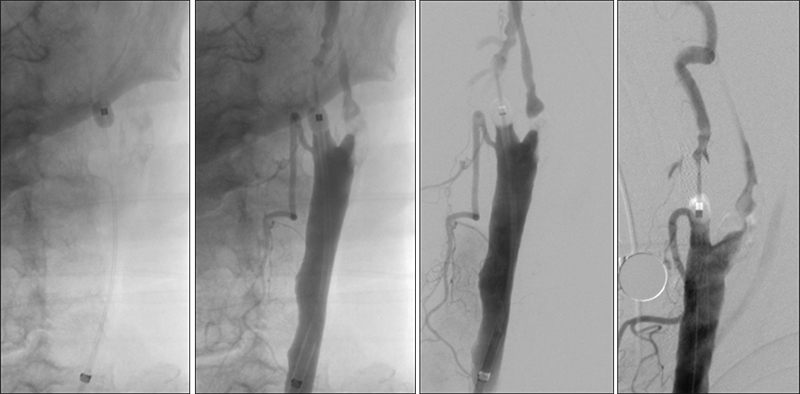

Εικόνα 7: Παρότι η αριστερή πλευρά είναι συμπτωματική, η παρουσία προσφάτων θρόμβων στον αριστερό καρωτιδικό βολβό αποτελεί αντένδειξη άμεσης αντιμετώπισης. Αποφασίσθηκε να τεθεί ο ασθενής σε θεραπευτικά επίπεδα αντιπηκτικής αγωγής με ηπαρίνη. Ταυτόχρονα, αντιμετωπίσθηκε πρώτα η δεξιά καρωτιδική στένωση με τοποθέτηση stent τύπου closed-cell με σύστημα προστασίας εμβόλων Spider.

Εικόνα 8 και 9: Έγχυση στην αριστερή κοινή καρωτίδα, μία εβδομάδα αργότερα υπό αντιπηκτική και αντιαιμοπεταλιακή αγωγή. Βλέπουμε βελτίωση της εικόνας στον αριστερό καρωτιδικό διχασμό. Συγκεκριμένα φαίνεται απορρόφηση των θρομβωτικών στοιχείων, με ελαφρά βελτίωση της ροής προς την μέση εγκεφαλική.